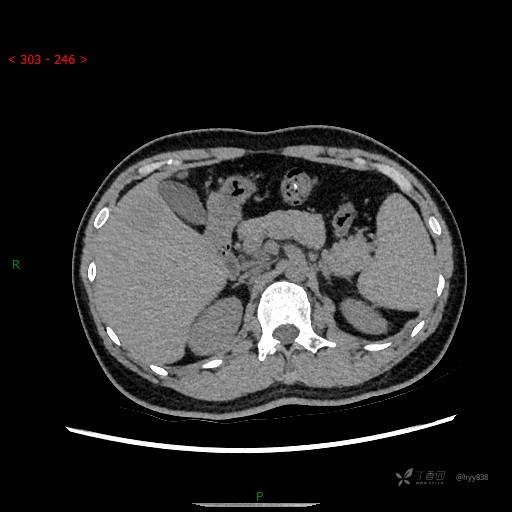

肝脏CT平扫